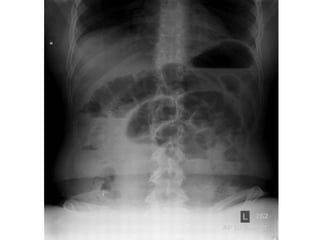

• La triada clásica de

obstrucción en el examen

radiológico es:

o Asas de intestino delgado dilatadas

(mayores a 3 cm)

o Niveles hidroaéreos

o Ausencia de aire distal

Signo del “grano de café”

Hallazgo clásico y diagnóstico del vólvulo sigmoideo en una radiografía simple de abdomen

• La triadaclásica de obstrucción en el examen radiológico es: o Asas de intestino delgado dilatadas (mayores a 3 cm) o Niveles hidroaéreos o Ausencia de aire distal

Signo del “granode café” Hallazgo clásico y diagnóstico del vólvulo sigmoideo en una radiografía simple de abdomen